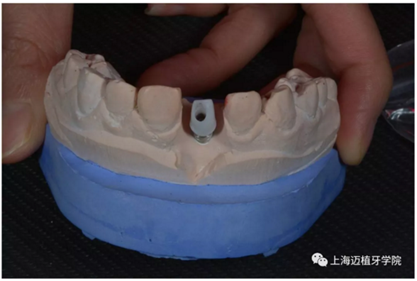

轉(zhuǎn)移模型

取工作模型

氧化鋯個性基臺